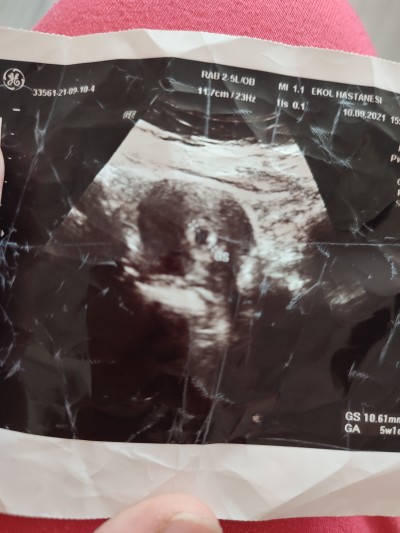

Kızlar merak ettim kese konumu diye birşey varmı karından bakınca ultrasonda sağda çıkarsa kız solda çıkarsa erkek diyorlar 6 7 8 haftalıkken benim kızımda sağımdaydi ultrasona bakınca dünde yine gittim bu bebeğimde sağimda ultrasonda ramzi ve nub teorisine göre diyorlar sizce doğrumu sadece merak ettim

Ssanki hafif sağa doğru benim

image

Yok sanki daha çok solda gibi 6 haftlik USG mi bu

(552 puan)

Ha ben böle bakışta sağda dedim solda mi yani ne bilim.5 haftalık burda 11 haftalıkken erkeğe benziyo dedi çıkıntısı var dedi.hatta kordon değilse ben bile gördüm yani:-)